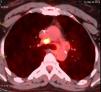

La paciente fue sometida a radioterapia postoperatoria (45Gy) y tratamiento hormonal (tamoxifeno) durante 12 meses. Dos años más tarde, se observaron algunas metástasis nuevas en los ganglios linfáticos axilares del lado derecho que fueron extirpados. Un año más tarde, un TAC torácico mostró múltiples ganglios linfáticos en el mediastino con captación positiva de FDG en el PET (fig. 1). La broncoscopia fue normal. Dado que el valor de SUV fue bajo, se repitió el estudio de FDG-PET 3 meses más tarde, que mostró un crecimiento estable de los ganglios linfáticos. Se realizó una biopsia de los ganglios linfáticos mediante mediastinoscopia que reveló un granuloma con células gigantes sin caseum compatible con sarcoidosis. La paciente fue tratada con corticoides con buen resultado.